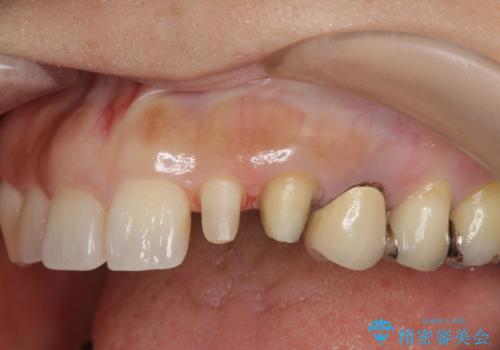

- 左上の前歯が小さく左右対称ではないのと、保険の前歯の被せ物のやりかえを希望して来院。

小さい前歯は、反対側と合わせた形にしました。

被せ物だけやりかえており、患者様のご希望もあり、根の治療や土台(コア)のやりかえは行なっていません。